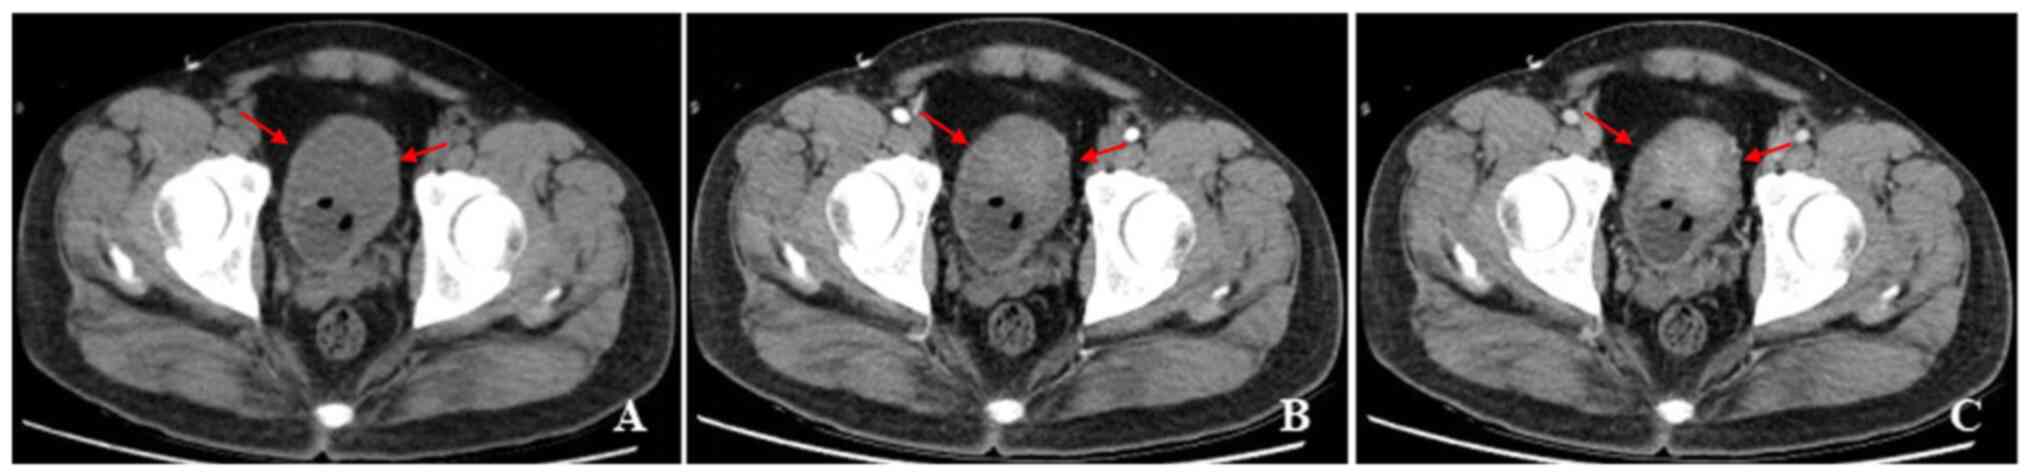

Figure 3

A 60-year-old woman with gross hematuria, painful urination, irregular blood clot. (A) Unenhanced CT scan of bladder showed a cauliflower-like soft-tissue mass with an endophytic growth pattern on the superior wall, with homogeneous density. (B-D) Contrast-enhanced CT scans revealed heterogeneous enhancement of the lesion and symmetrical change in the center of the lesion. CT, computed tomography.

The CT findings showed that 8 (89%) patients had one tumor and 1 (11%) patient had multiple tumors. The bladder IMT size ranged from 1.3x2.1 to 4.8x5.1 cm2. Tumors occurred in the posterior wall in 2 (22%) patients, 5 (30%) patients had tumors occurred in the superior wall, 1 (11%) patient had tumors occurred in the front wall, and 1 (11%) patient had tumor occurred in the left wall (Fig. 2, Fig. 3, Fig. 4 and Fig. 5). An endophytic growth pattern (Fig. 3) was identified in 4 (44%) patients, an exophytic growth pattern (Fig. 2) was observed in 2 (22%) patients, and a mixed growth pattern (Fig. 5) was revealed in 3 (33%) patients. The tumor manifests morphologically as either polypoid (n=5), or cauliflower-like (n=1) soft-tissue mass with a wide base in the cavity, or a limited thick-walled (n=3) in the bladder. The tumor margins were smooth (n=8) or lobulated (n=1) and the tumor boundaries were either clear (n=7) or ill-defined (n=2).

The unenhanced CT examination of the lesions revealed either low density (n=4), iso-density (n=3), or slightly high density (n=1), and density was either homogeneous (n=3) or heterogeneous (n=6). The enhanced CT examination of the lesions showed either ring-shaped (n=3) or heterogeneous (n=6), and the degree of enhancement was either significant (n=6), or moderate (n=3). The enhancement pattern was persistent (n=9). In addition, all polypoid and cauliflower-like soft-tissue masses showed a symmetrical change in the center of the lesion after enhancement on the CT image.